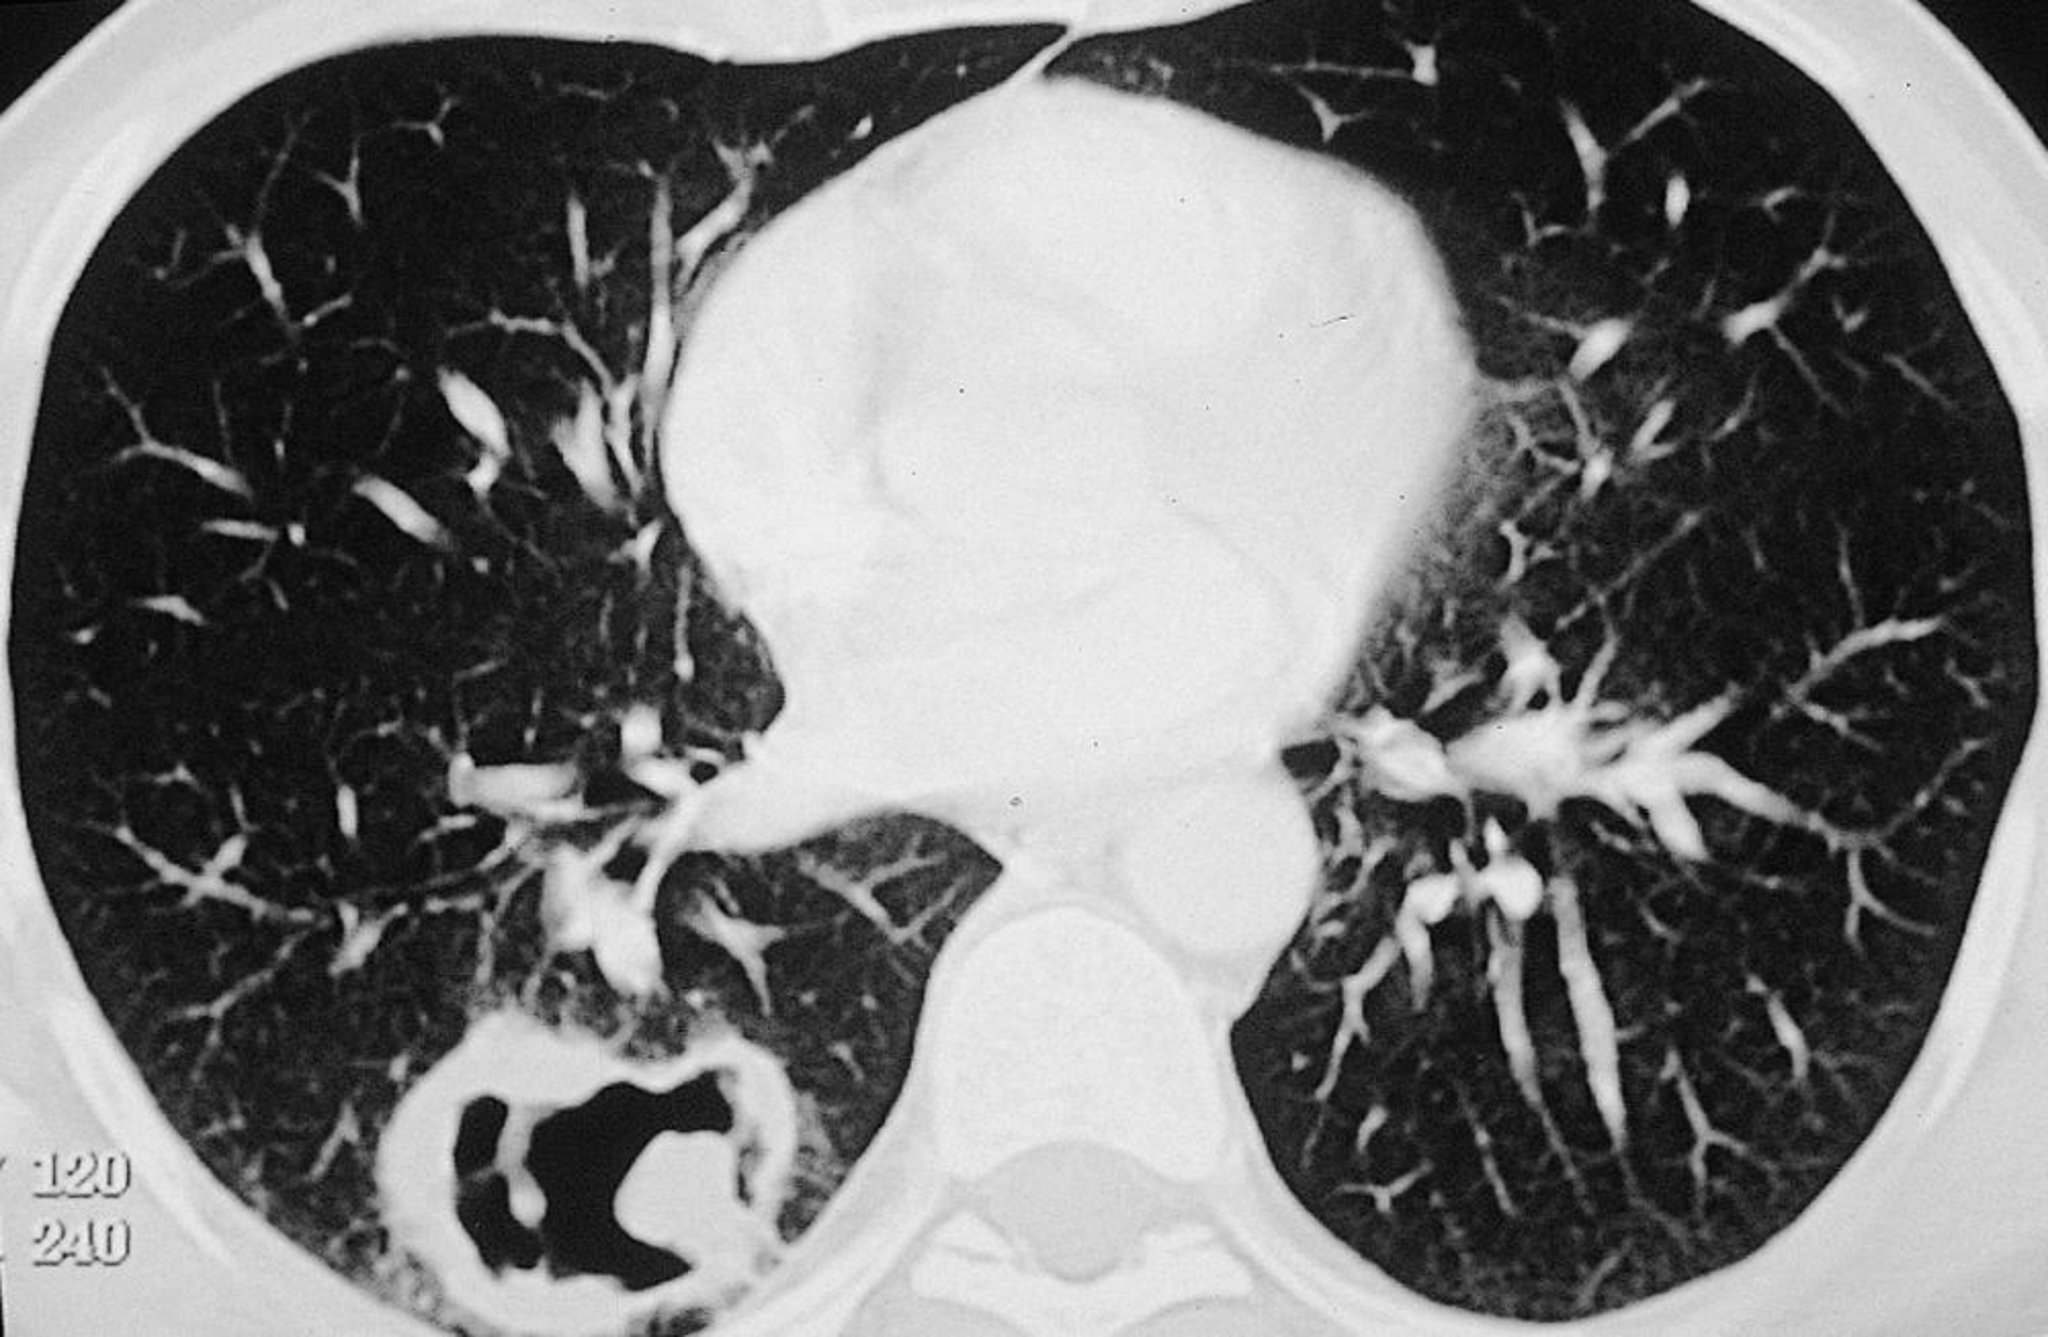

Grande lesione cavitaria nel polmone destro in un paziente con granulomatosi con poliangioite.